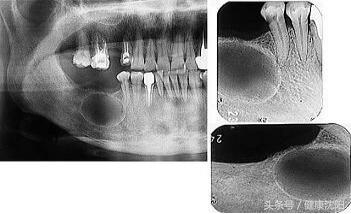

3.口腔颌面及头颈部良恶性肿瘤的根治:包括血管瘤、淋巴管瘤及脉管畸形,甲舌囊肿、颌骨囊肿及各类软硬组织囊肿,舌癌、牙龈癌、颊癌、腭癌、口底癌、上颌窦癌等恶性肿瘤。

3.干槽症。干槽症是拔牙创急性感染的一种类型,以下颌后牙多见,特别是在下颌阻生第三磨牙拔除术后。

在正常情况下,即使是翻瓣去骨拔牙手术,其创口的疼痛2~3天后会逐渐消失。如果拔牙后2~3天后出现剧烈的疼痛,疼痛向耳颞部、下颌下区或头顶部放射,用一般的止痛药物不能缓解,则可能发生了干槽症。临床检查牙槽窝内空虚,或有腐败变性的血凝块,呈灰白色。在牙槽窝壁覆盖的破死物有臭味,用探针可直接触及骨面并有锐痛。颌面部无明显肿胀,张口无明显受限,下颌下可有淋巴结肿大、压痛。

颌骨囊肿